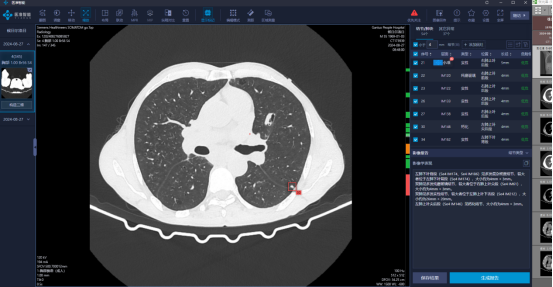

AI賦能,讓肺小結(jié)節(jié)無(wú)處藏身

肺結(jié)節(jié)是肺癌的“信號(hào)燈”,是臨床上一種常見(jiàn)的現(xiàn)象。但惡性結(jié)節(jié)早期發(fā)病比較隱匿,一位資深的影像診斷醫(yī)師,需要十幾分鐘到幾十分鐘不等才能完成包含幾百?gòu)埛尾緾T影像的閱片診斷,且人眼識(shí)別還容易產(chǎn)生漏診。今年8月,甘洛縣人民醫(yī)院為有效提高肺結(jié)節(jié)的檢出率,引進(jìn)了AI影像輔助診斷系統(tǒng),主要就是針對(duì)肺結(jié)節(jié)篩查。

圖:AI影像輔助診斷系統(tǒng) “過(guò)去全靠人工,肺結(jié)節(jié)從檢查到出報(bào)告,基本在2小時(shí)左右。采用了AI輔助診斷系統(tǒng)后,效率提升了一倍?!?/span>醫(yī)院放射科主任全清林在引入AI影像輔助診斷系統(tǒng)后感慨該技術(shù)可以明顯減少繁雜、重復(fù)的處理工作,大大提升放射科醫(yī)師的診斷效率。 近年來(lái),我院放射科每日接診肺結(jié)節(jié)患者40名左右,醫(yī)院影像醫(yī)師診斷肺結(jié)節(jié)需手動(dòng)測(cè)量結(jié)節(jié)大小,再依據(jù)經(jīng)驗(yàn)出具診斷報(bào)告,工作量大不說(shuō),還易漏診。相較于傳統(tǒng)閱片模式,人工智能輔助的閱片模式可以大幅度降低血管旁、微小結(jié)節(jié)、淡磨玻璃結(jié)節(jié)漏診概率。其實(shí),AI影像輔助診斷系統(tǒng)可精準(zhǔn)、秒級(jí)檢出3mm-3cm肺結(jié)節(jié)及占位性病變,提供結(jié)節(jié)長(zhǎng)短徑、體積、密度、成分組成等多維分析結(jié)果,自動(dòng)生成結(jié)節(jié)良惡性程度預(yù)測(cè)。再同時(shí)加入診斷醫(yī)師的審核,雙重把關(guān)從真實(shí)意義上實(shí)現(xiàn)精準(zhǔn)診斷、精準(zhǔn)醫(yī)療,極大縮短患者的檢查結(jié)果等待時(shí)間。該系統(tǒng)引進(jìn)近一個(gè)月時(shí)間,醫(yī)院胸部CT檢查900余人次,AI影像輔助診斷發(fā)現(xiàn)肺結(jié)節(jié)約400人次。 圖:AI診斷出肺結(jié)節(jié) AI賦能,“秒測(cè)”骨齡 生長(zhǎng)發(fā)育是兒童獨(dú)有且極其復(fù)雜的過(guò)程。骨齡,作為反映骨成熟度的指標(biāo),當(dāng)進(jìn)行青少年兒童生長(zhǎng)發(fā)育監(jiān)測(cè)的時(shí)候,可以根據(jù)骨齡來(lái)評(píng)價(jià)和分析青少年兒童體格生長(zhǎng)是否與實(shí)際年齡一致,從而對(duì)兒童剩余身高進(jìn)行早期評(píng)估。 骨骼成熟度一般通過(guò)檢查左手腕骨X射線正位片來(lái)進(jìn)行評(píng)估。傳統(tǒng)骨齡評(píng)估需要影像診斷醫(yī)師觀察所拍片子左手掌指骨、腕骨及橈、尺骨下端的骨化中心的發(fā)育程度,再與標(biāo)準(zhǔn)的骨齡X線圖譜做比較來(lái)確定骨齡。這種傳統(tǒng)方法費(fèi)時(shí)費(fèi)力并且容易受到閱片醫(yī)師主觀因素影響,同一張X光片,不同的醫(yī)師閱片后可能會(huì)得出不同的結(jié)果。 我院引進(jìn)兒童生長(zhǎng)發(fā)育智能評(píng)估系統(tǒng)后,可以快速精準(zhǔn)全面多參數(shù)的分析,提供出骨齡評(píng)價(jià)報(bào)告。該系統(tǒng)采用目前唯一雙標(biāo)準(zhǔn)(中華05和TW3)AI檢測(cè)算法,具備目標(biāo)骨骺智能識(shí)別、分級(jí)以及骨齡計(jì)算,并自動(dòng)生成結(jié)構(gòu)化圖文報(bào)告等系統(tǒng)化、全方位的先進(jìn)功能,可有效提高醫(yī)生的工作效率和準(zhǔn)確率。AI系統(tǒng)從8月11日上線至今,完成了骨齡檢測(cè)15例。 AI賦能,心電“神器” AI賦能醫(yī)療不僅可提供診斷參考依據(jù),在實(shí)際運(yùn)用中還有自動(dòng)預(yù)警提示。“您有新的危急報(bào)告!”這是甘洛縣人民醫(yī)院心內(nèi)科移動(dòng)心電設(shè)備發(fā)出的心電圖預(yù)警提示。甘洛縣自“心電一張網(wǎng)”打通后,共鋪設(shè)有34臺(tái)心電檢查設(shè)備,覆蓋全縣域所有公立醫(yī)院,該設(shè)備上的AI診斷系統(tǒng)能對(duì)遠(yuǎn)程上傳的心電圖進(jìn)行輔助數(shù)值測(cè)量,提升醫(yī)生出報(bào)告的效率。同時(shí),針對(duì)危急診斷還會(huì)有預(yù)警提示,提升初診癥狀不典型患者相關(guān)診斷的及時(shí)性。依托人工智能的自動(dòng)分析與預(yù)警服務(wù),自今年3月心電一張網(wǎng)啟用至今,全縣心電圖AI診斷共報(bào)告危急值200余例,有效提升全縣心電系統(tǒng)診斷的準(zhǔn)確性和工作效率,方便醫(yī)院與基層醫(yī)療機(jī)構(gòu)及時(shí)建立聯(lián)系,為患者提供更快捷的醫(yī)療服務(wù),提高基層診療質(zhì)量。 圖:護(hù)士正使用移動(dòng)心電圖機(jī)為患者檢查